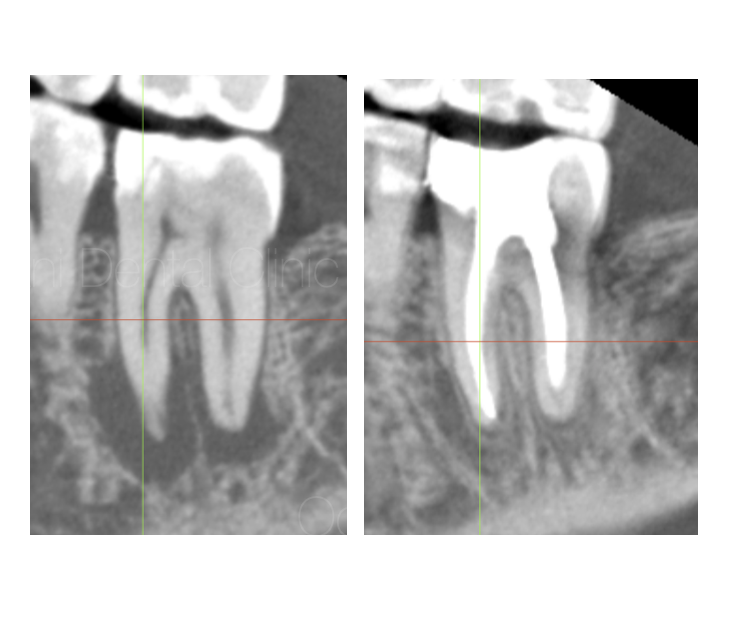

根の治療(根管治療)の診療ブログカテゴリー追加